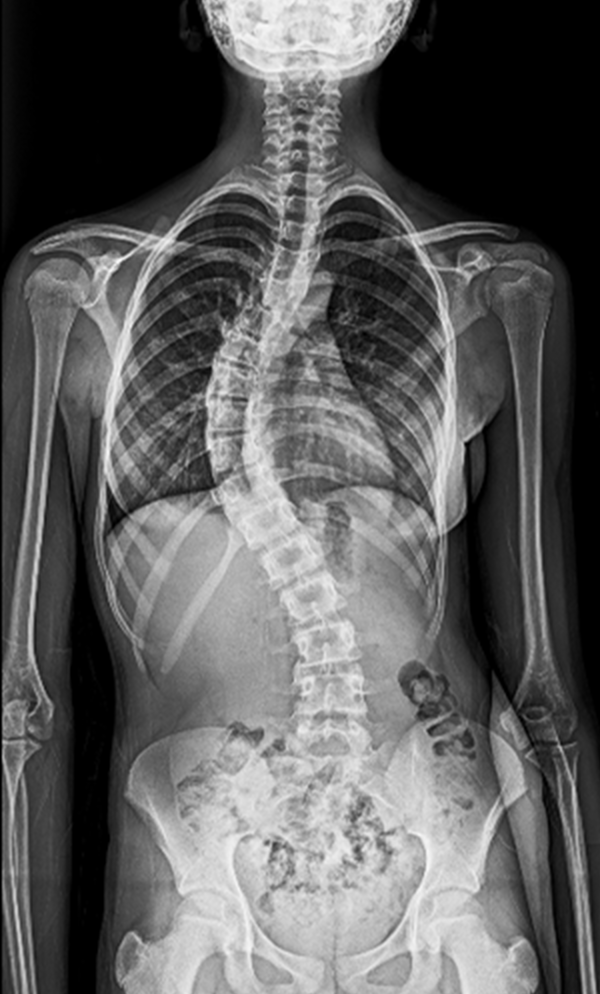

BEYOND RECOVERY : REAL STORIES

Gallery : Before - After